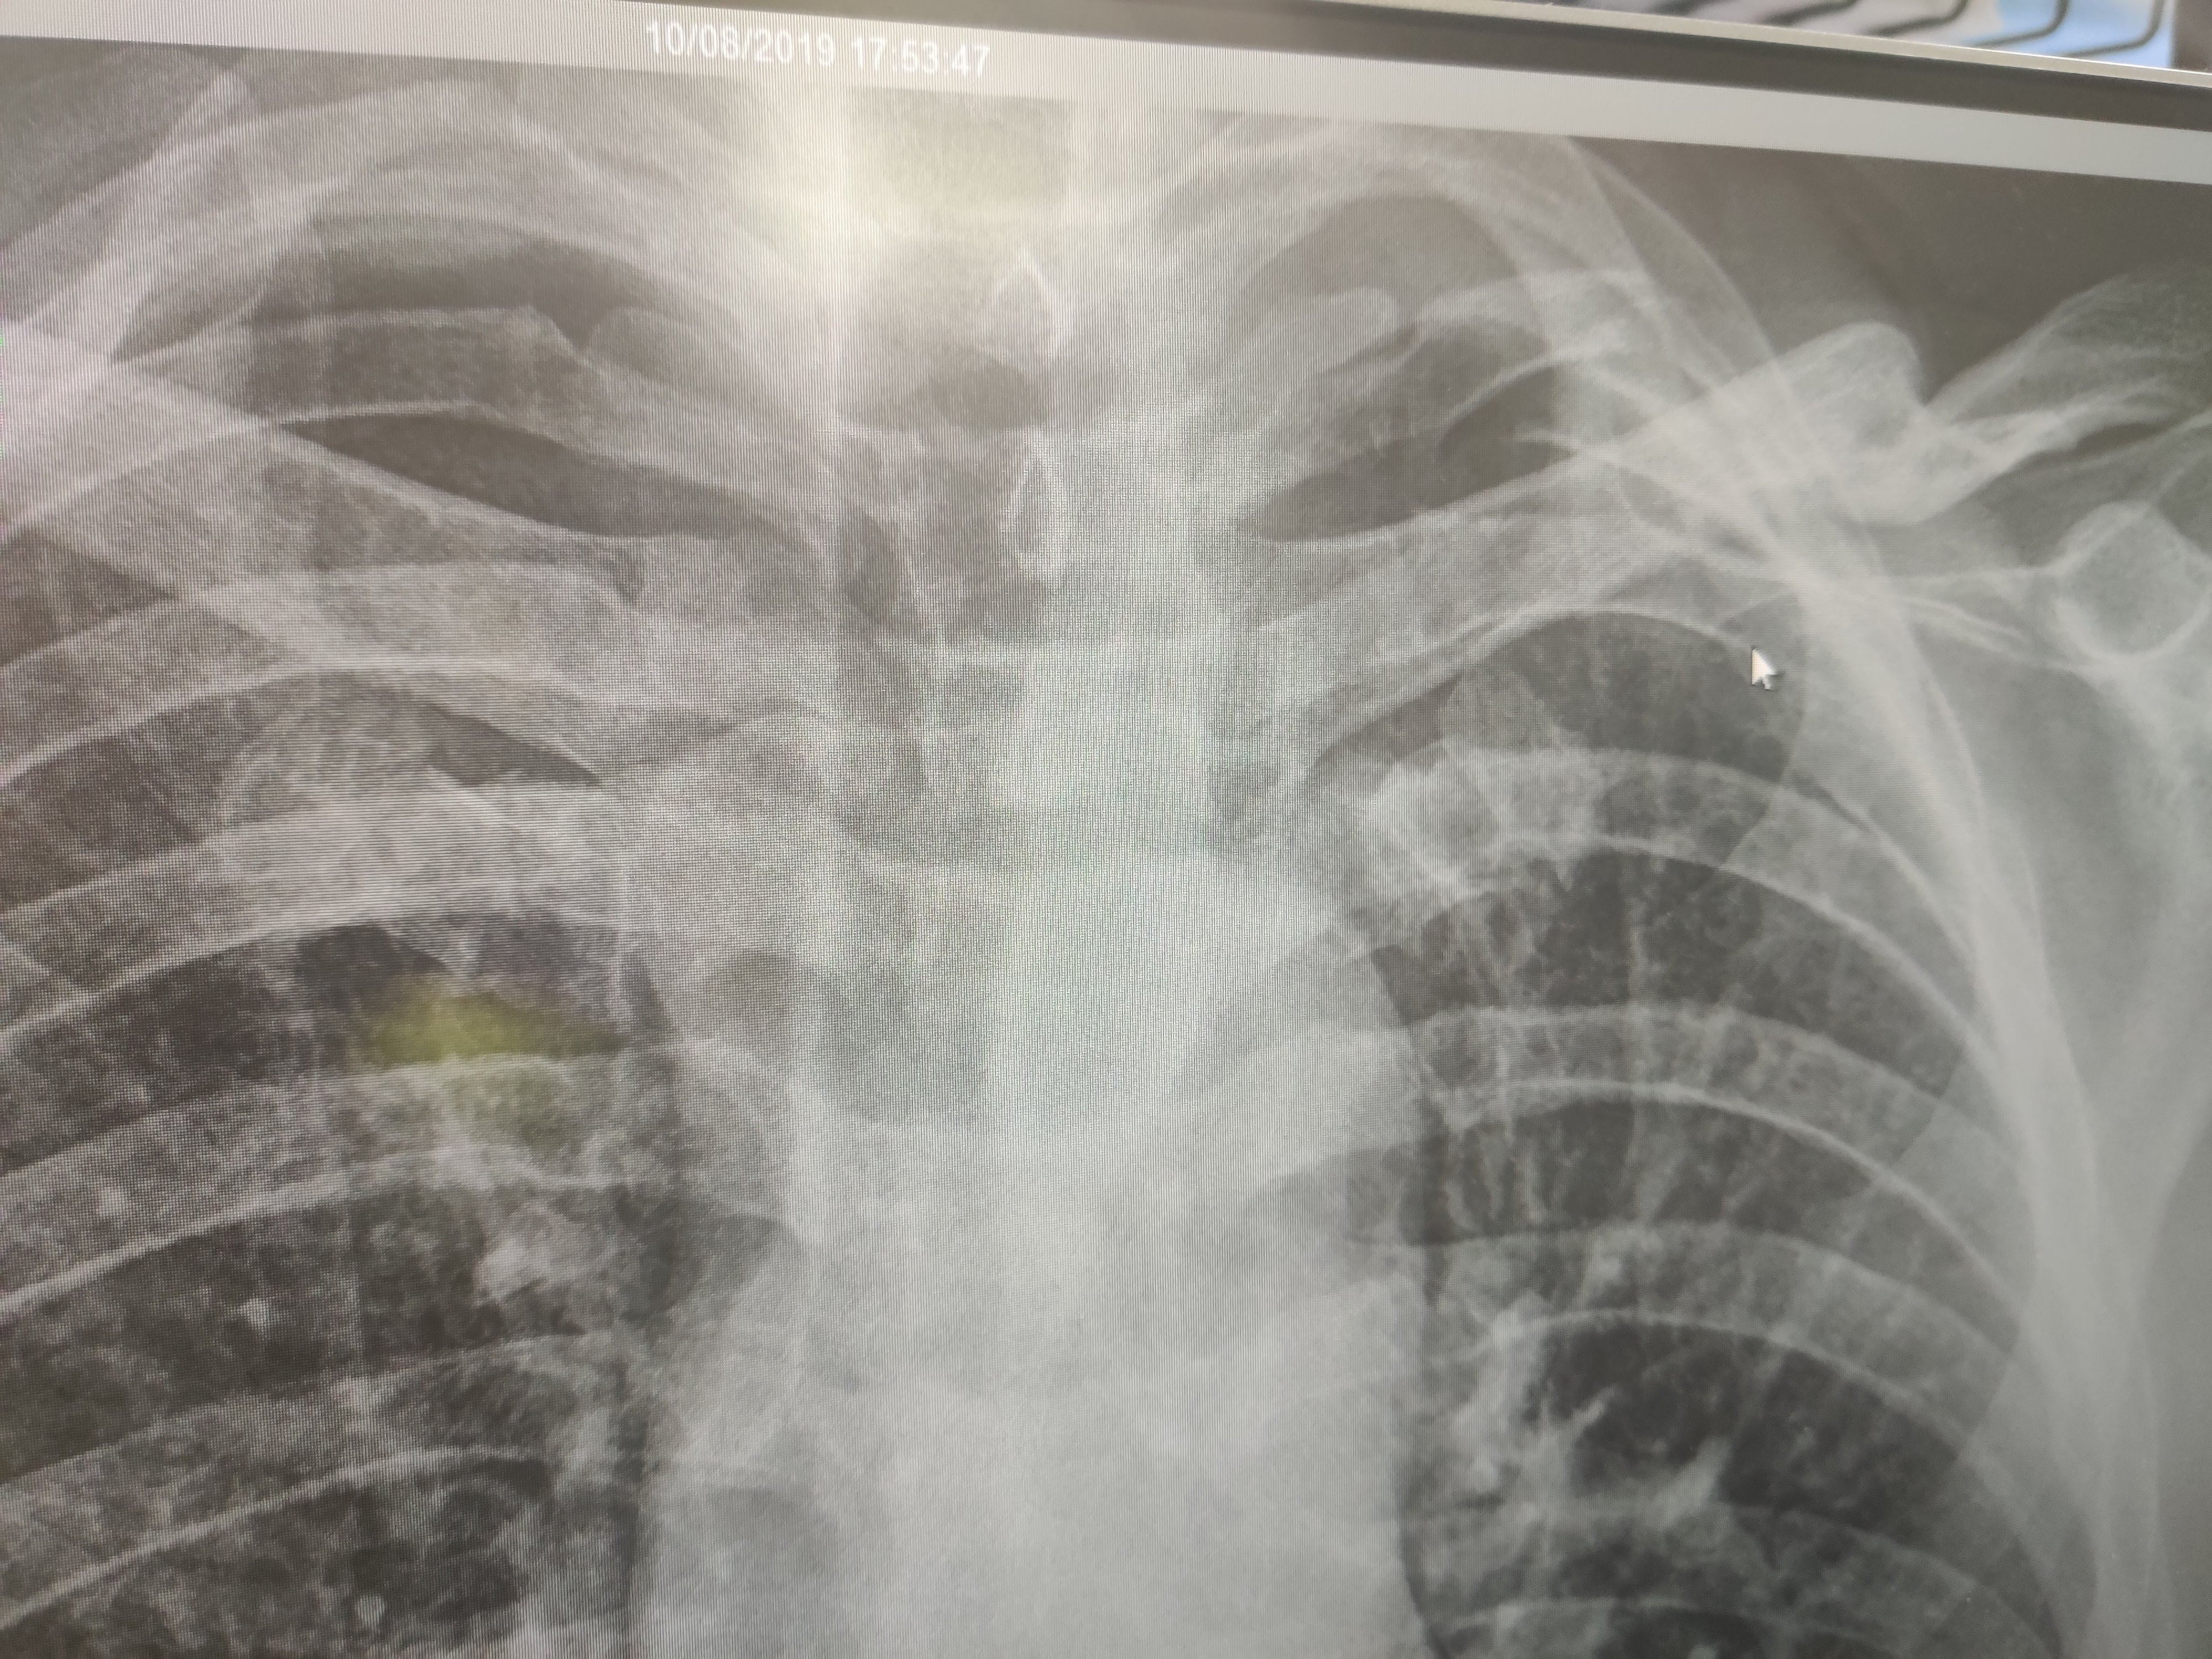

X-Ray

To cut a long story short (the long version is on the Propel Bikes FB page) I had a crash which resulted in me breaking 3 ribs & damaging muscles, ligaments & all sorts of soft tissue.